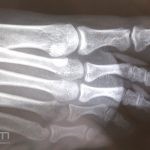

Diagnóstico:

Clínico, radiografia.

RX: proliferação óssea subungueal.